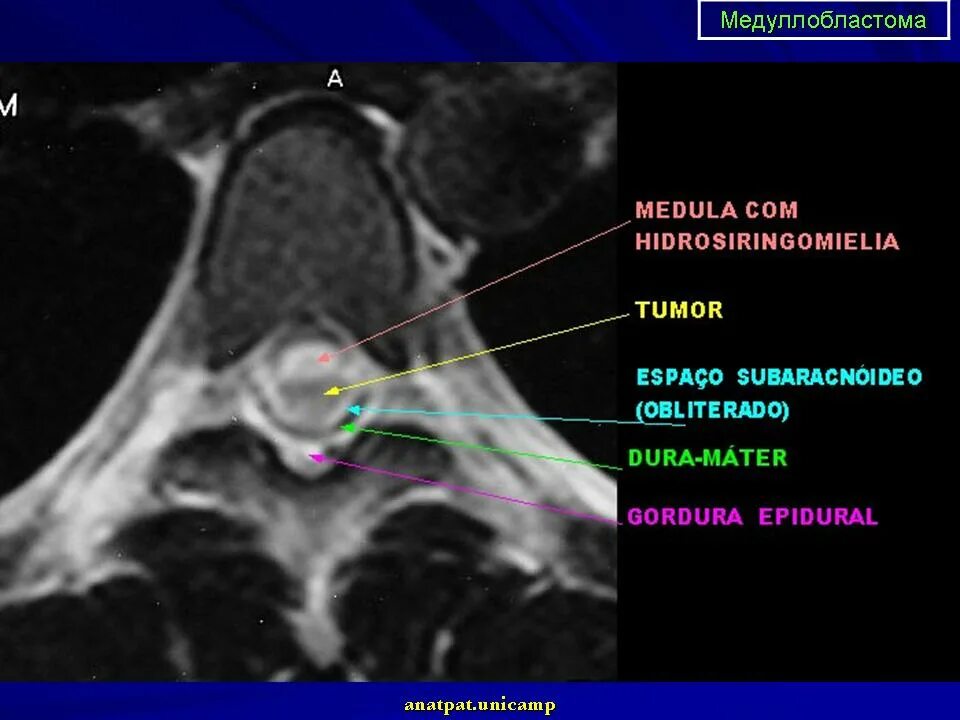

Медуллобластома это